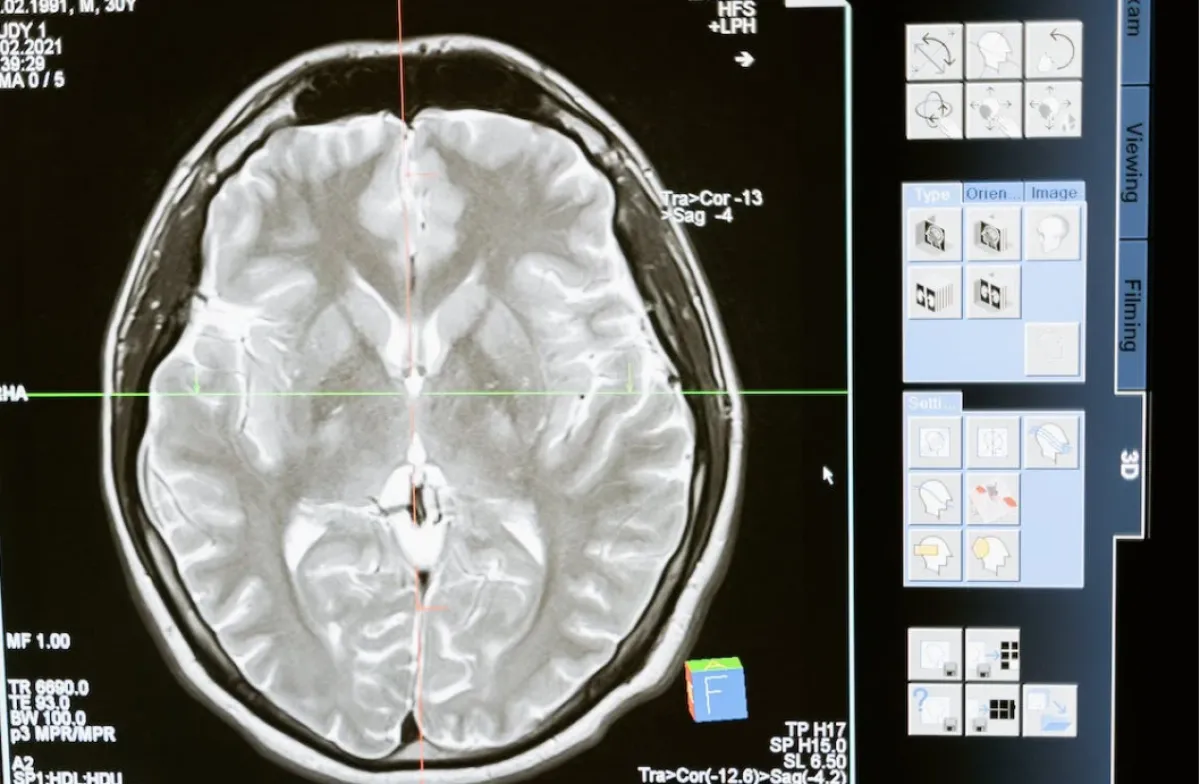

ووفقا لما ذكر في صحيفة البيان الإماراتية، فقد اعتمد المشروع على استخدام نظام الـ" BCI" غير الجراحي، والذي يقدم حلولا للطب النفسي يساعد الأطباء على علاج المرضى المصابين بأمراض مثل الاكتئاب والحزن المزمن، عبر الاعتماد على نظام للارتجاع العصبي الذي يستخدم EEG لفك تشفير وتعديل المشاعر البشرية.

وتابعت موضحة أن المشروع يفوق فاعلية النتائج المترتبة على تناول أدوية الاكتئاب وغيرها، كونه يعمل على تنظيم إشارات الدماغ باستخدام تكنولوجيا تسمى واجهة الدماغ الحاسوبية "BCI" مع نظام ذكاء اصطناعي يكتشف 3 أنواع من المشاعر في دماغ الإنسان وهي الحزن، والفرح، والمشاعر الطبيعية، تم تطويره من قبل الطالبات.

واختتمت "اليماحي" حديثها مشيرة إلى أن النظام يعمل بدقة 92.3%، لاستشعار الإشارات الدماغية، وبالتالي التعرف على مشاعر الإنسان بدقة سواء كانت اكتئاب أو حزن مزمن، وبالتالي يجد الطريقة المثلى لإعادة تنظيم إشارات الدماغ وتحسين حالتهم المزاجية والنفسية.